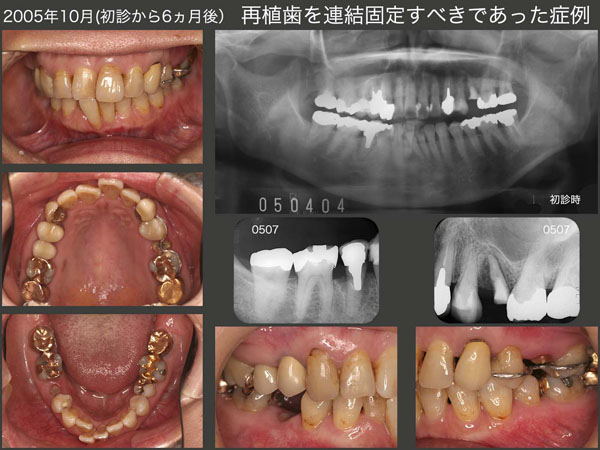

6.再植歯を連結固定すべきであった症例

初診は2005年4月,61歳女性.主訴は左上5のクラウン脱落.まず右下4のう蝕処置(生切・09年抜髄)および歯周基本治療を行った.スライドは05年10月の状態であるが,左上5は矯正的挺出中,右下5は歯根破折にて抜歯した直後.

2006年1月に右下1を右下5部に移植した.左上5は矯正的挺出終了後暫くしてフィステルが生じてしまった.感染根管処置を施したが,根尖が開かなかったので,06年4月に再植を行った.またドナーとして抜去した右下1の空隙を埋めるため,さらに上顎前歯の審美的改善を期待して歯科矯正を行った.07年4月に治療は全て終了した.

この当時は,歯を連結固定すると清掃性が落ちることから,極力連結固定を避ける気持ちが強かった.もちろん暫間被覆冠で咀嚼できる等の反応をみて判断していたが,再植,移植した歯は若干動揺が残るので,当該歯には大きい咬合力が加わらないから安全であると高をくくっていた.このケースも暫く反応をみたが特に問題がなかったので,再植した左上5および移植した右下5を単独植立のままとした.